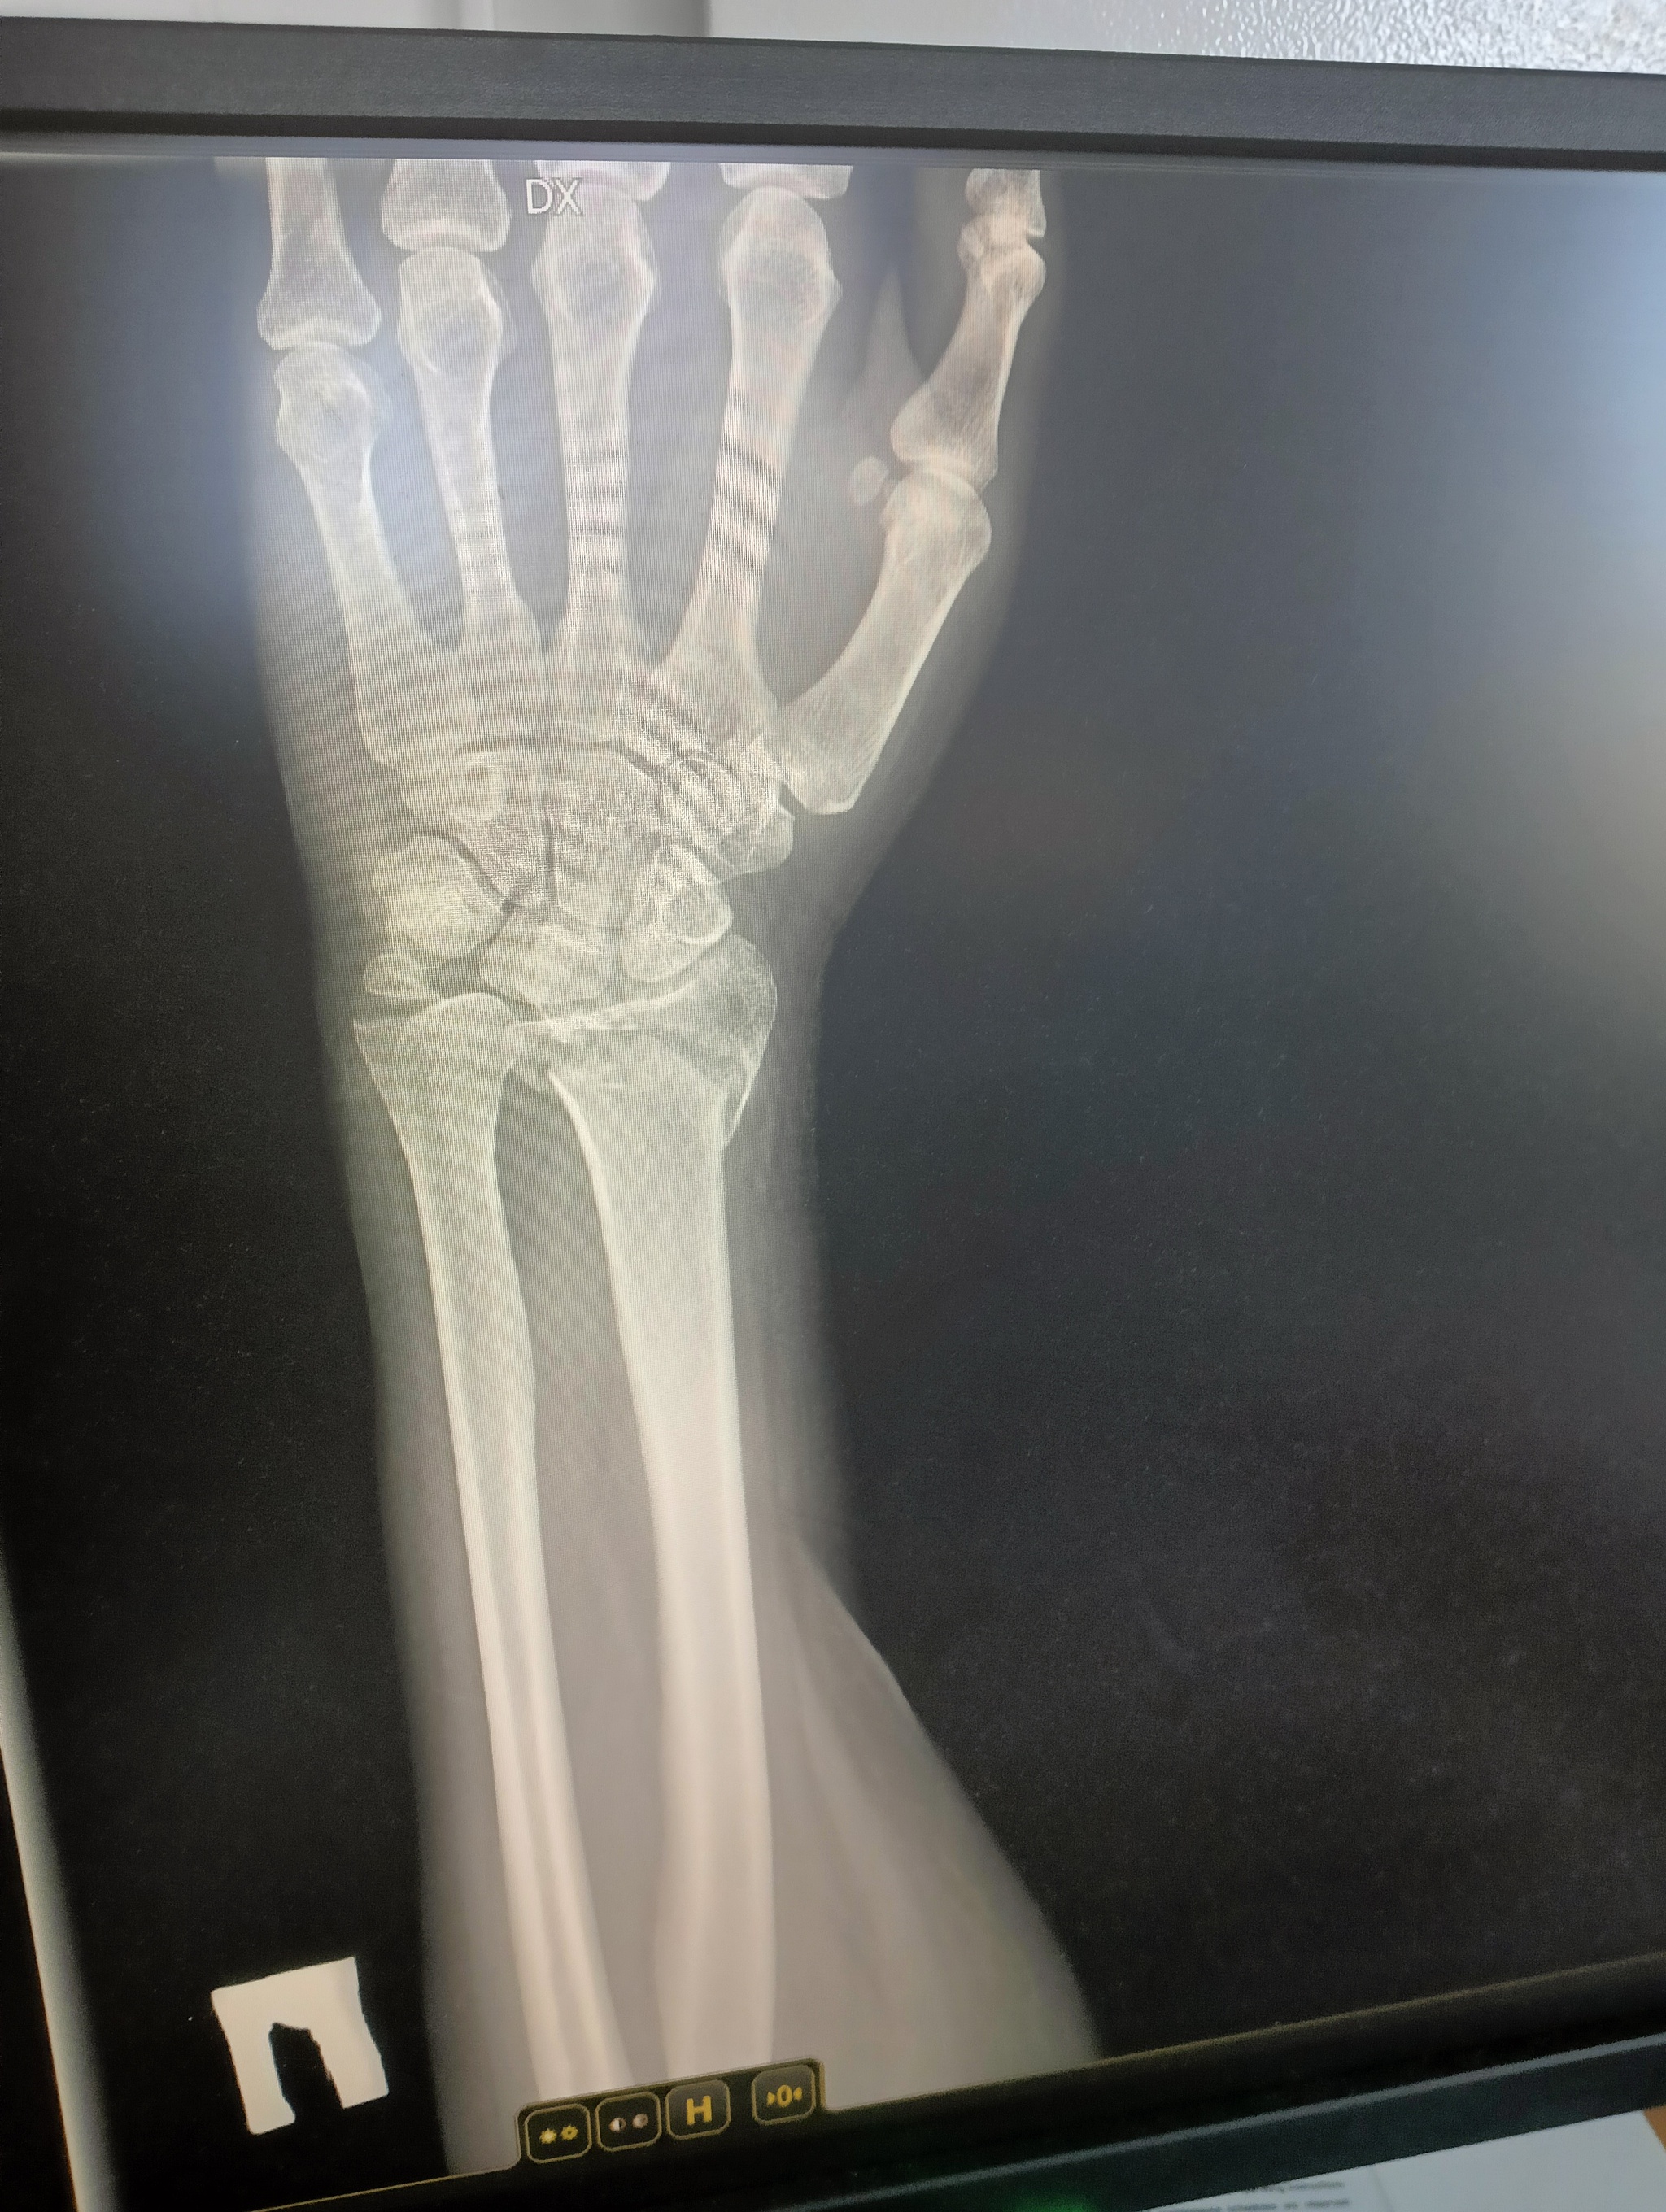

22 июля я неудачно упала и получила оскольчатый перелом дистального метафиза лучевой кости со смещением отломков более чем на 1/2 ширины диафиза. Открытый перелом шиловидного отростка локтевой кости. Была месяц в гипсе, но ничего не срослось. Диастаз костных отломков стал до 4 мм. Локтевая ушла в сторону на 5 мм. На 3 месяц после перелома мне сделали операцию, поставив титановую пластину. Сегодня сделала ренген и получила вот такой результат: Застарелый сомнительно консолидирующийся перелом дистального метафиза правой лучевой кости в условиях накостного МОС. Помимо отрыва шилообразного отростка локтевой кости, видно, имеется разрыв дистального радио-ульнарного сочленения.

верхние ффото через 2 месяца после перелома, потом после операции и 2 нижние - сегодня